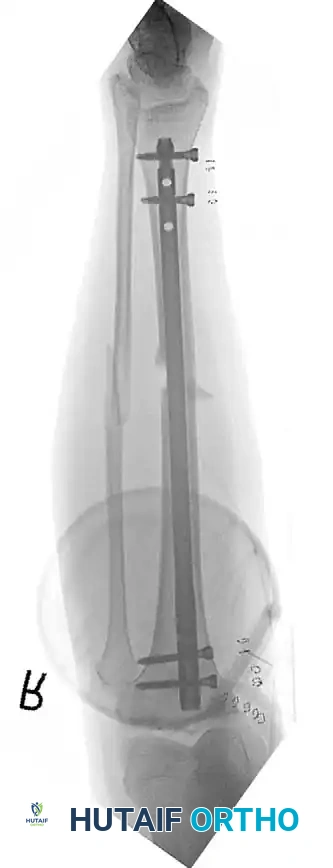

POSTOPERATIVE PROTOCOLS AND CONVERSION TO DEFINITIVE FIXATION

The goal of DCO is to bridge the patient through the acute physiological crisis. Once the patient's lactate has cleared, coagulopathy is reversed, and inflammatory markers have peaked and begun to trend downward (typically between days 5 and 10), the patient is optimized for conversion to definitive fixation.

Lerner et al. noted complications of pin track infection with emergency external fixation; however, Harwood et al. demonstrated that there is no significant increase in deep infection rates if the conversion from external fixation to intramedullary nailing is performed in a timely manner—defined strictly as within 14 days of the initial injury.

If pin sites show signs of superficial infection (erythema, purulent discharge), the external fixator should be removed, the pin tracts aggressively debrided and over-reamed, and the patient placed in skeletal traction or a cast until the soft tissues sterilize, prior to definitive internal fixation.